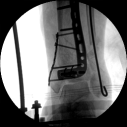

初步復(fù)位后X線

2.CO接骨機器人持續(xù)牽引維持復(fù)位,選擇前外側(cè)切口對前外側(cè)骨塊進(jìn)行撬撥復(fù)位,并用克氏針進(jìn)行臨時固定。C臂透視復(fù)位滿意,放置兩塊鋼板進(jìn)行固定。